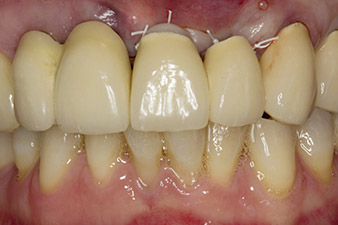

In this case study, the situation was resolved with an implant at position 22 in the first procedure and an additional one at the position of the extracted tooth 23 later in the course of the treatment. The second implant was inserted following successful osseointegration of implant 22. The revised bridge was reinserted until implant 23 healed in place and the shaping for the permanent restoration was complete. The advantages of this gradual approach include the implants’ being able to accept loads more resiliently and mature hard and soft tissues (5).